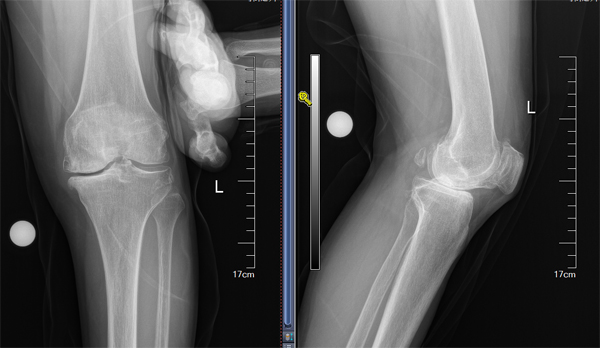

膝关节单髁手术技术从零到有

王伟教授入住骨科后,定期对关节组医师进行授课及专业培训,充分评估患者病情,严格掌握手术适应症,仔细规划术前方案,指导洛阳市中心医院骨科顺利开展膝关节单髁置换手术,实现了该院膝关节单髁置换技术零的突破。目前,该院骨科已能常规开展该技术,促进了洛阳市中心医院关节技术的发展。单髁置换手术是虽然是较为传统的膝关节终末期关节炎的治疗手段之一,早期由于各种原因导致这种优良的手术方式与全膝关节置换术比较发展较为缓慢,但随着近年置换适应症把握、关节假体设计及关节材料的进步多种原因,使单髁置换术成优良的微创保膝治疗手段,在国内外得到广泛的推广。单髁置换术应用于合适的终末期骨关节炎患者后,相比全膝关节置换具有,创伤小,恢复快,病人满意度高等优势,同样得到广大的患者的认可和首选。由于单髁置换讲究更高的置换精度,要求精细,而准确的手术操作,对手术医师的素养具有更高要求,只有具有一定手术量积累的医生,才能获得良好效果,减低手术风险。洛阳中心医院单髁置换手术方式的开展,代表在保膝,微创治疗中迈上一个新台阶。